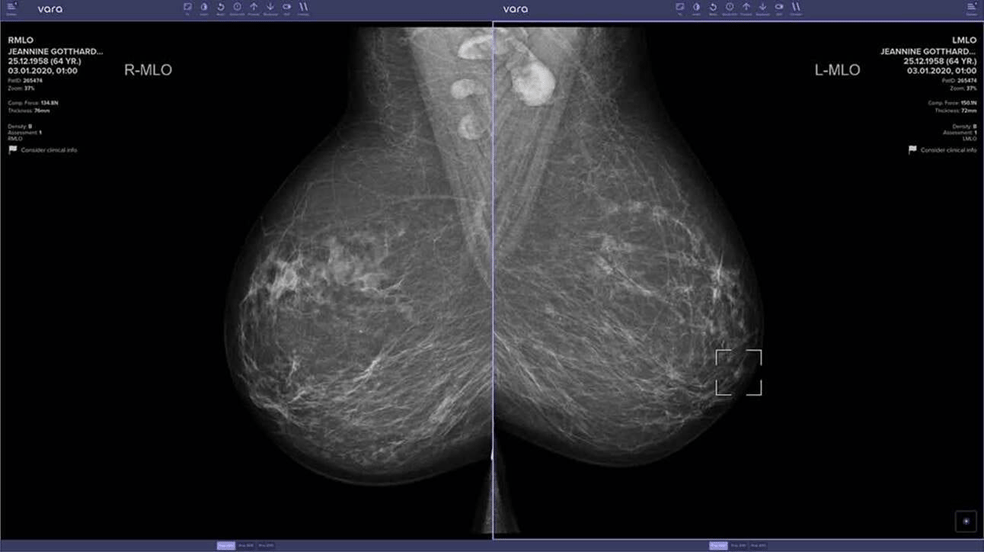

AI boosts cancer detection in new study

Researchers from the University of Lubeck in Germany just published a new study featuring the largest-ever real-world implementation of AI in breast cancer screenings, finding that AI can improve cancer detection rates by over 17%. Here are the highlights:

The study involved 119 radiologists who could voluntarily choose whether or not to use AI, with over 460,000 women undergoing screenings.

AI-supported radiologists achieved a cancer detection rate of 6.7 per 1,000 screenings, a 17.6% improvement over traditional readings.

For biopsies ordered, 65% of AI-assisted readings confirmed cancer compared to 59% without, showing improved accuracy in recommending procedures.

The AI also helped reduce workload by enabling 43% faster reading times while maintaining accuracy, going from 30 seconds per case to just 16.

AI is quickly proving its worth across nearly all aspects of medicine and healthcare — not only designing and creating new treatments but also enabling doctors to provide more accurate care. (link)